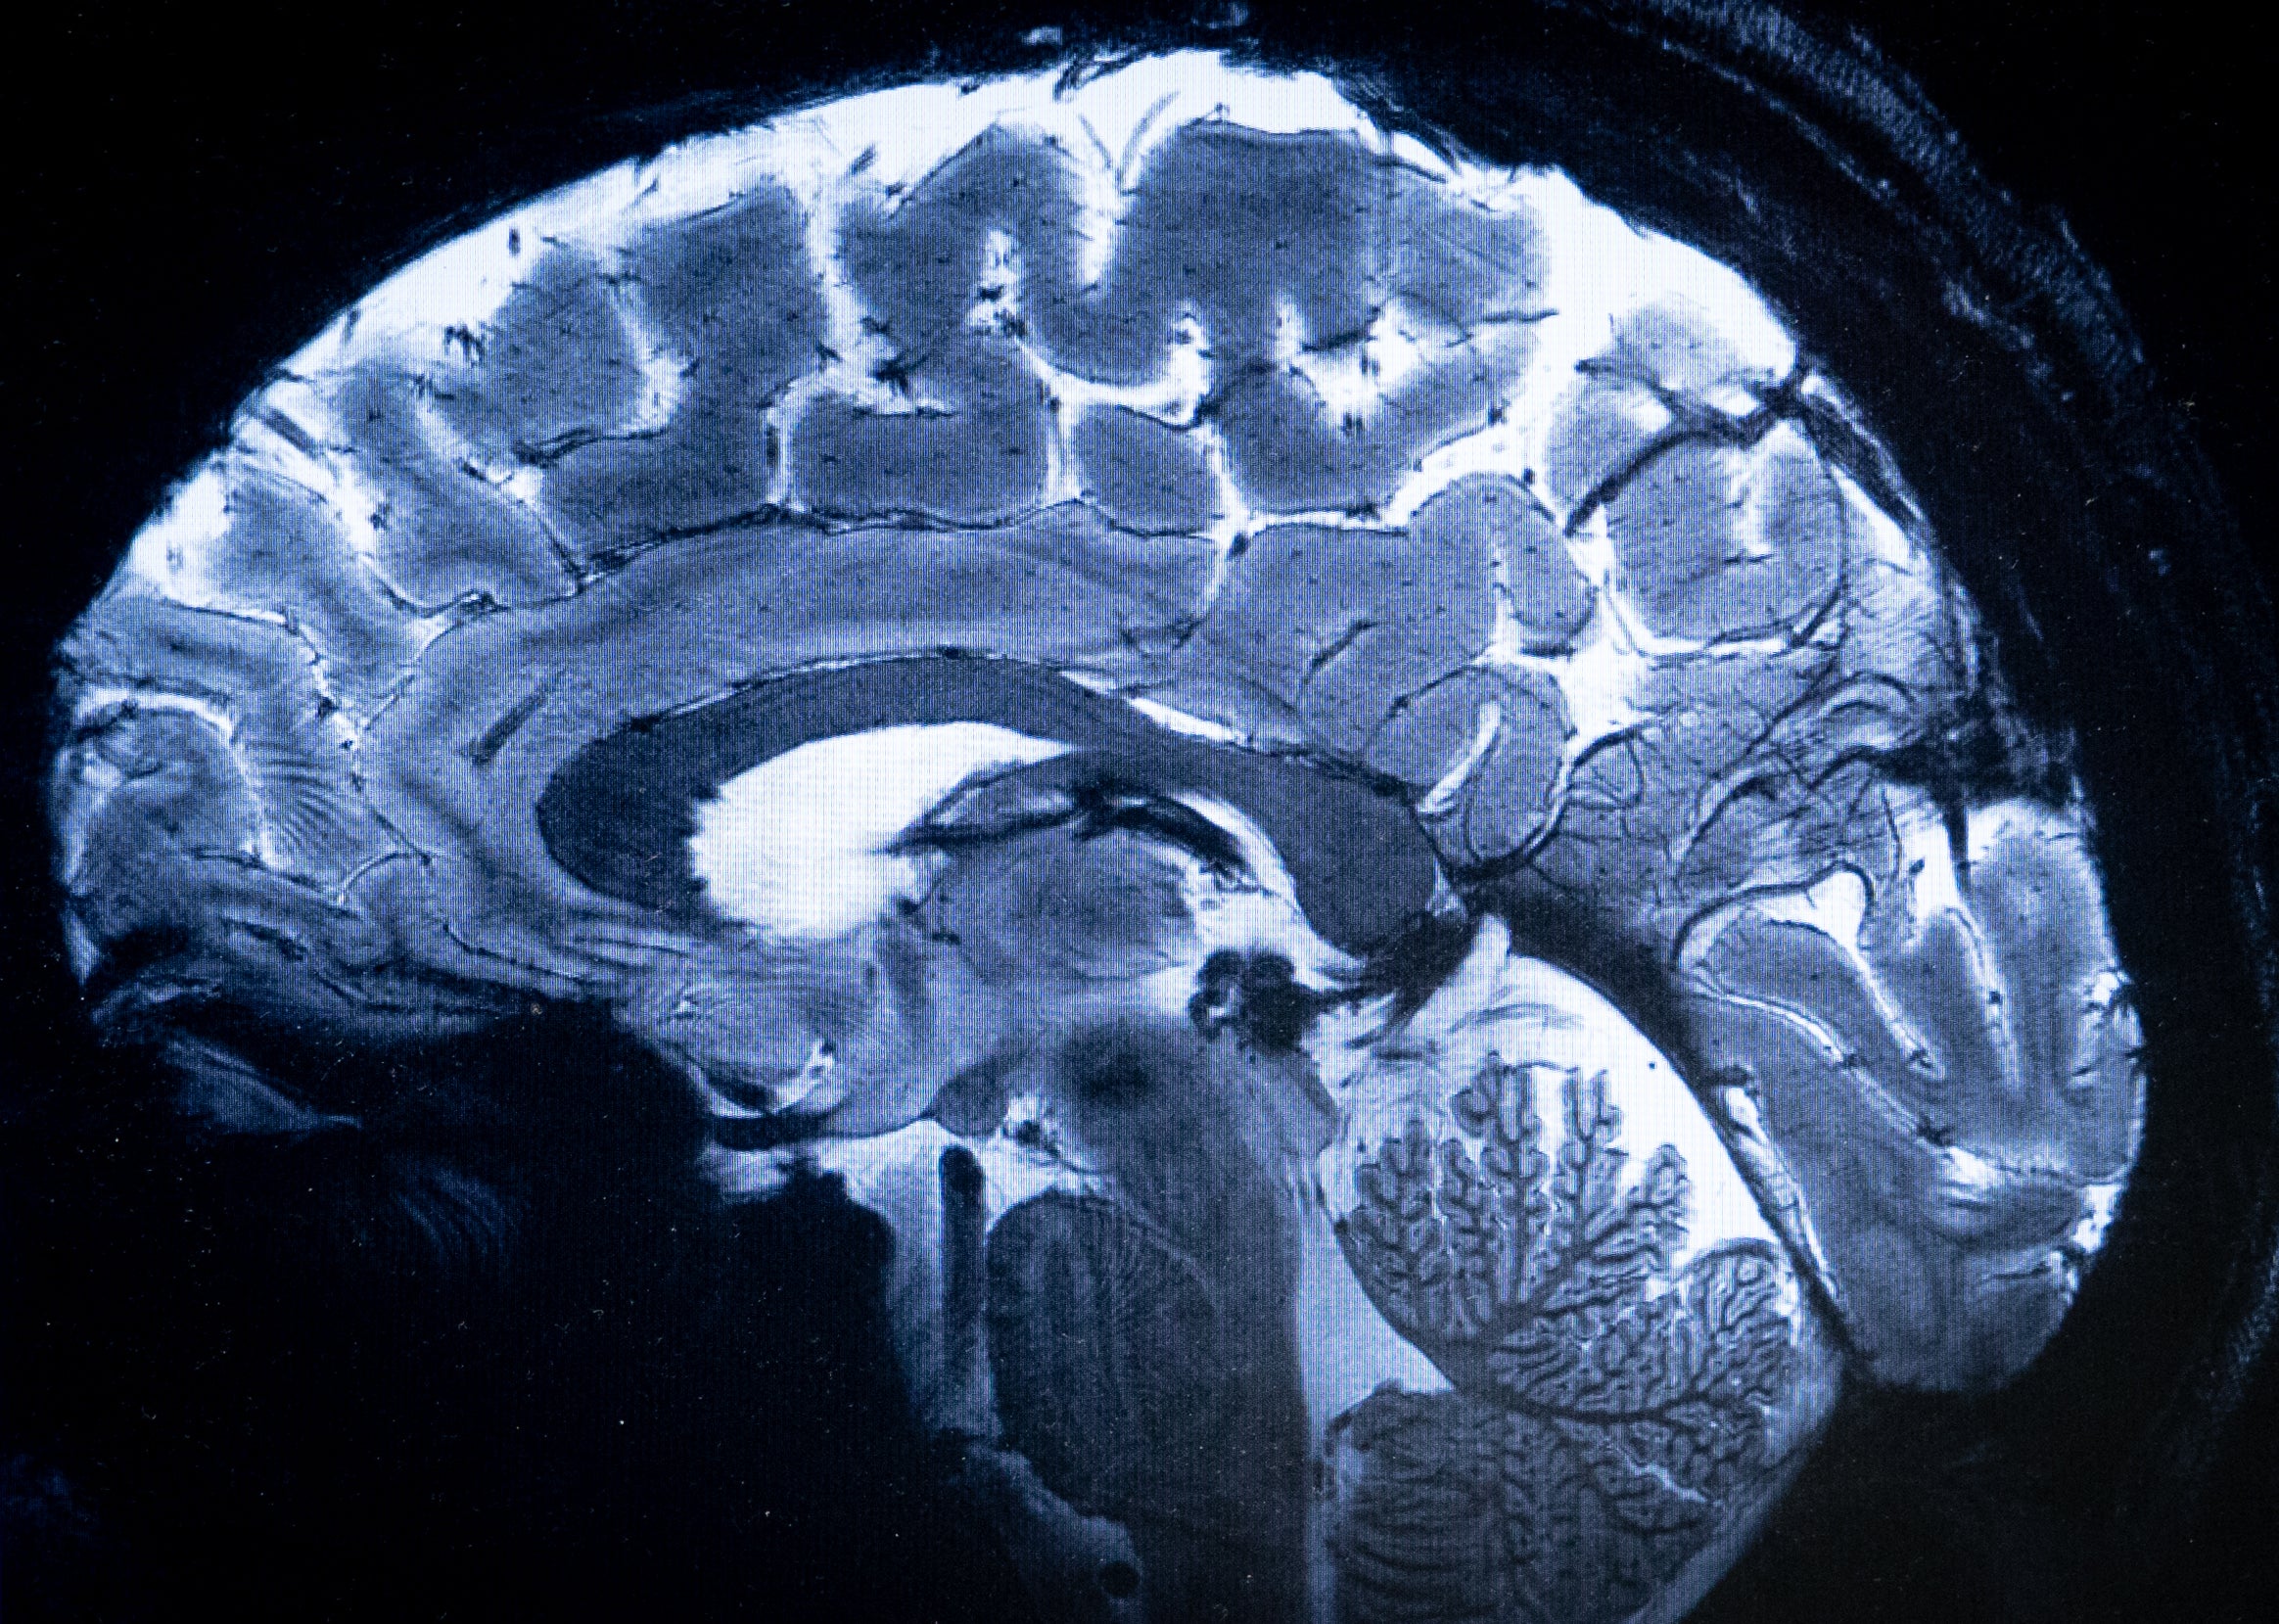

Se cree que el cuerpo del Dr. Dituri rejuveneció desde el punto de vista biológico, ya que tenía telómeros más largos, una estructura de los cromosomas a veces relacionada con la longevidad.

Según declaró a WKMG News, de Orlando: “Ahora tengo 56 años. Mi edad extrínseca [biológica] era de 44 años. Cuando salí del agua, mi edad extrínseca era de 34 años”.

“Así que mis telómeros se alargaron. En realidad, rejuvenecí cuando estaba bajo el agua”.

Además, se redujeron en un 50 % todos los marcadores de inflamación en sus análisis de sangre.